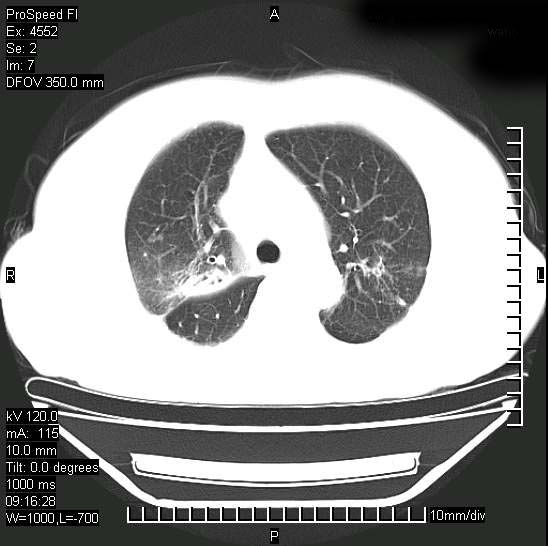

标题: CT15528:女性,79岁,近几日晚上高热,39度,仍咳少量血

十几年前曾患肺结核,一周前突咳血约100ml,中性粒细胞稍高,诊断两上肺陈旧结核,下肺炎症,给予抗炎治疗,近几日晚上高热,39度,仍咳少量血,4天前ct及今天ct上传。

今天ct